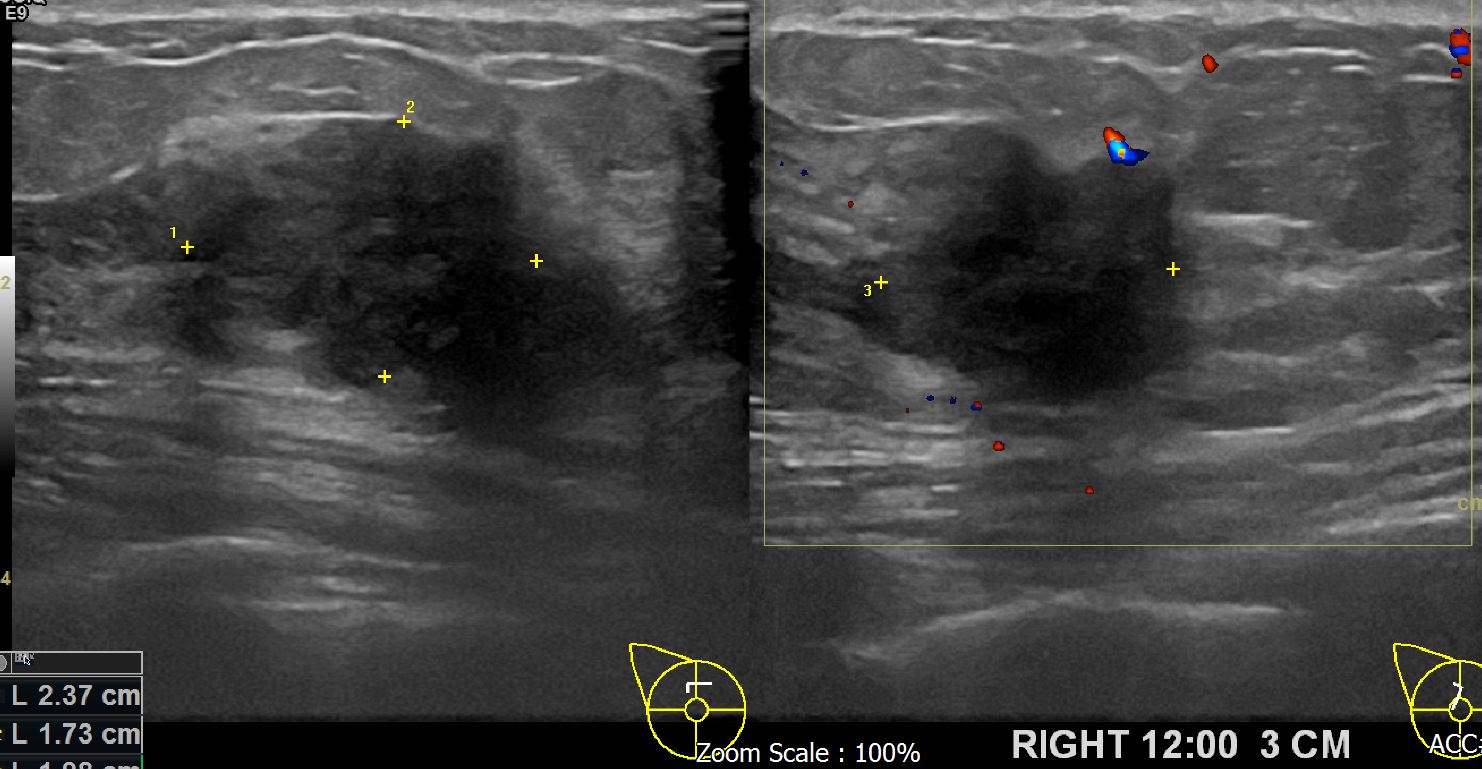

아산유외과 개원후 617번째 유방암진단

상기환자 외부검사상이상소견으로 본원 내원해주신 40대 여성으로 우측의심스러운혹있어 조직검사시행후 유방암진단되셨습니다.